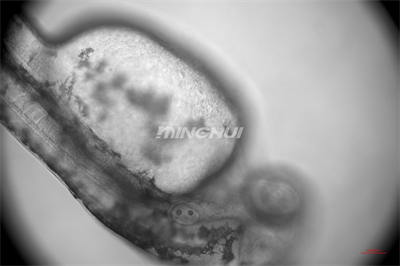

20倍半復(fù)消色差物鏡觀察的效果

1.半復(fù)消色差物鏡系統(tǒng):配備4×、10×、20×半復(fù)消色差物鏡,有效消除色差與球差,尤其在20倍率下仍能保持心臟邊緣成像銳利,清晰呈現(xiàn)心室收縮舒張過程中心肌細(xì)胞的運(yùn)動細(xì)節(jié)。